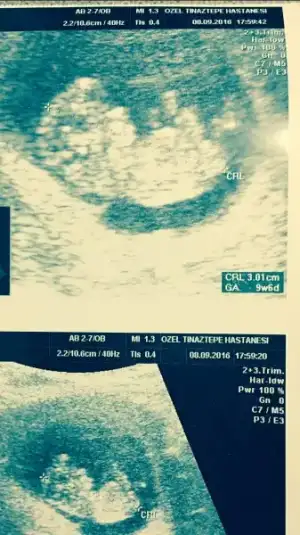

Maşallah yakışıklı Paşa'ya :) çok sevindim canım güzel haberlerine. Ben de nifty testi araştırdım daha kesin bir test üstelik tarama değil tanı testi. Doktoruma sormadım daha alacağın bilgileri paylaşırsan sevinirim. Bu arada ben de bebişimin son fotosunu yollayayım müsait olunca bir Tahmin alayım kız hissediyorum ben ilk defa :)

Eklentiler

• image.webp

image.webp

28 KB · Görüntüleme: 87